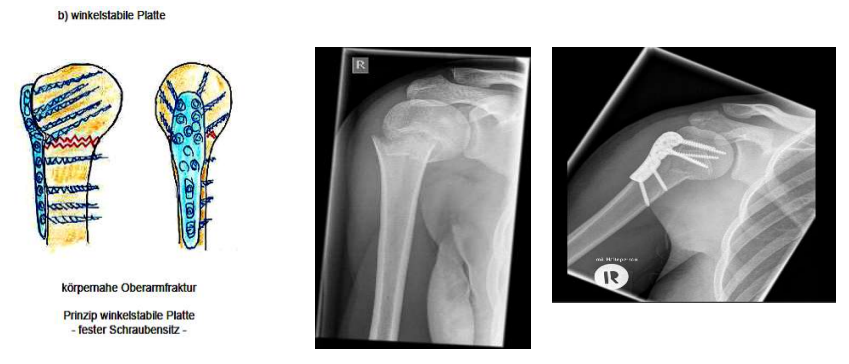

Operative Frakturbehandlung

Plattensysteme

Besonderheit Winkelstabile Platte

in Plattenlöchern gewinde eingebaut die zu Schrauben passen

Schrauben können sich weniger bewegen → stabilere Osteosynthese

Nachteil: zu stabil - Platten Wandern aus und Schrauben evtl die Knochen

Oberarmbruch - Subcapital

Nagel soll Position fixieren und Knochen zum heilen bringen

mit vielen, zielgerichteten Schrauben Knochen an richtigen Platz bringen